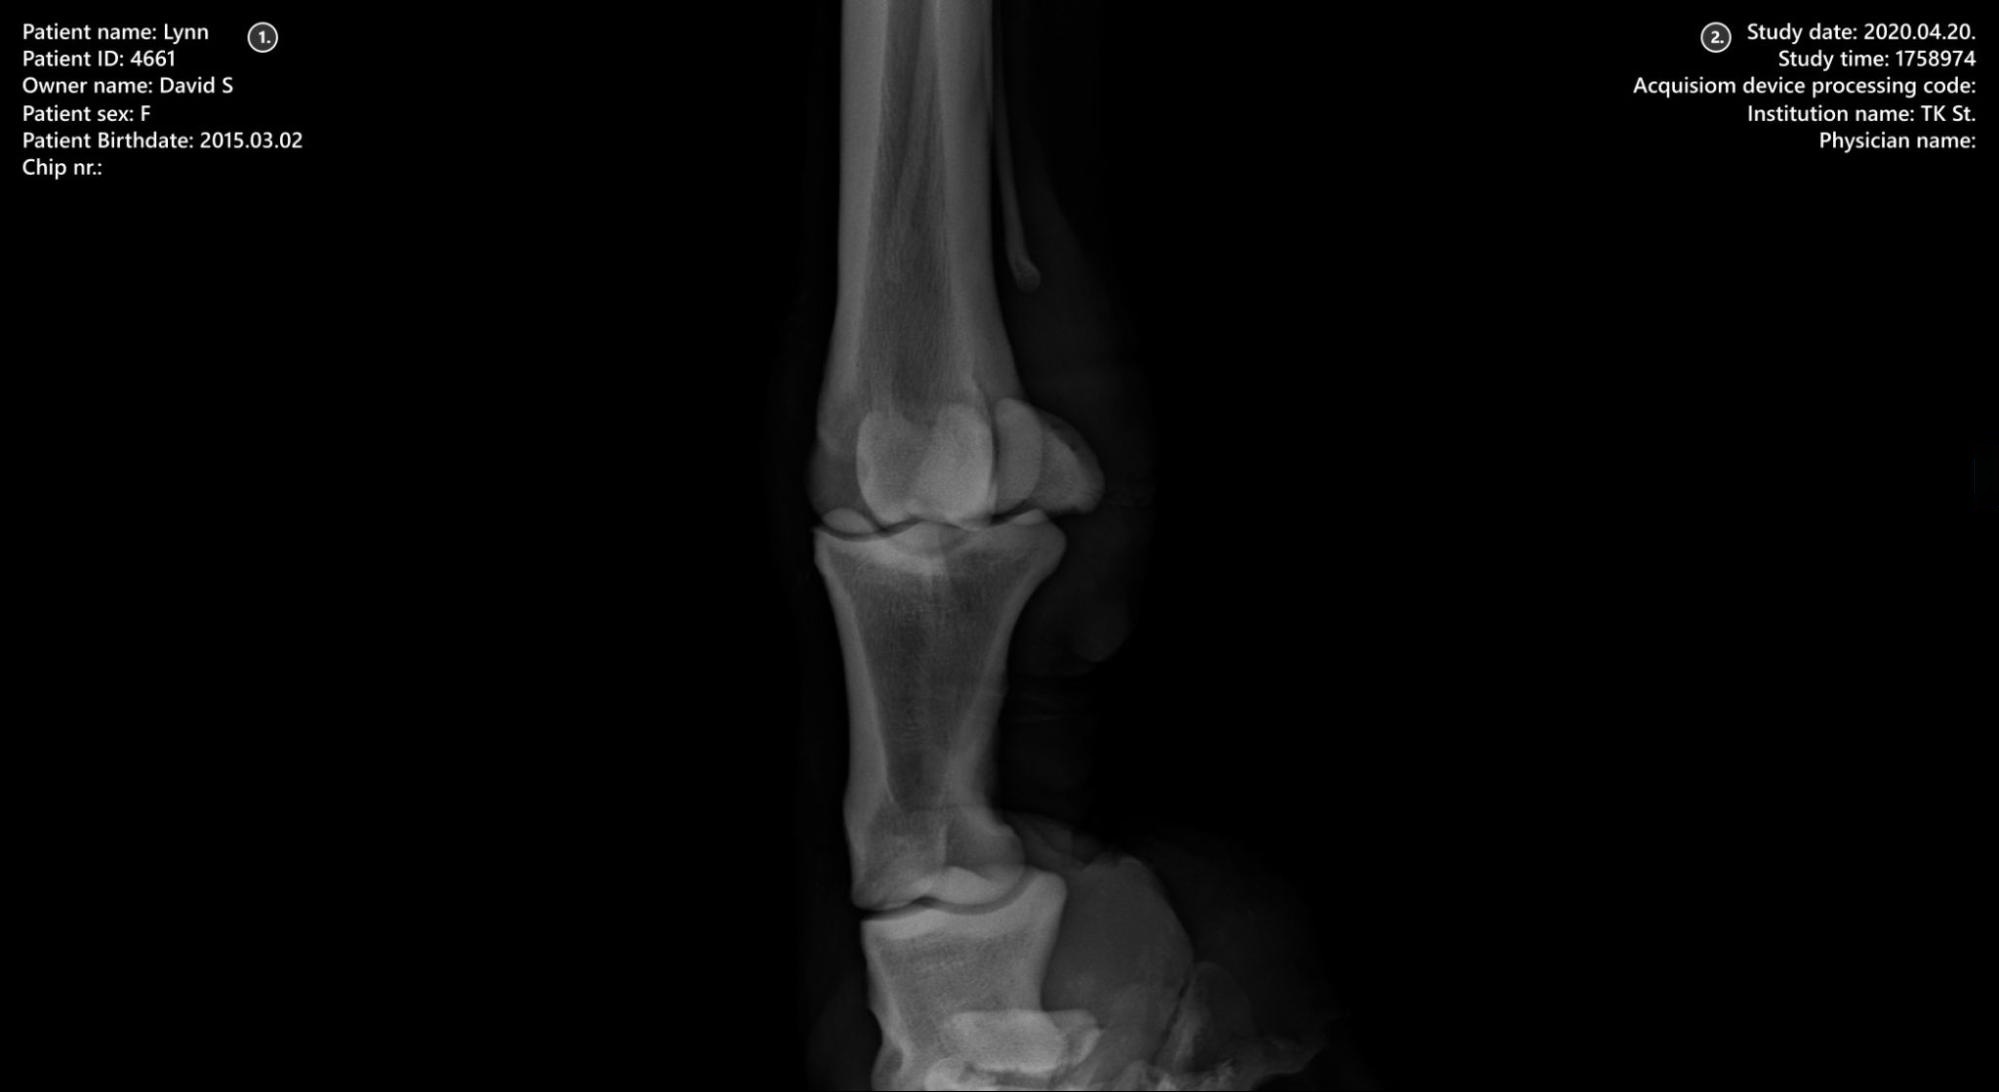

Sections of the VisioVIEW Viewer¶

The VisioVIEW Viewer consists of several sections, each tailored to a specific purpose. Below is a detailed description of each section.

Viewer Area¶

Patient information

Study information